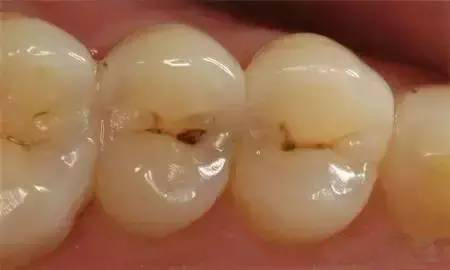

龋齿俗称虫牙、蛀牙,是细菌性疾病。蛀牙的主要原因是口腔不洁,牙菌斑长期堆积侵蚀造成的。出现多颗蛀牙,说明您的口腔卫生较差,没有及时补牙和改善口腔卫生,所以才会出现第二颗、第三颗蛀牙,且龋坏程度也会继续加深,建议您尽快对蛀牙进行补牙治疗。

浅龋早期龋齿仅波及牙釉质,在釉质的表面出现大小不一的黄褐色斑点,一般无症状,常常不易被察觉,大多数患者在口腔检查时才发现。这一期的龋齿成为浅龋。中龋当龋坏进一步发展,波及牙本质浅层时,称为中龋。此时龋病进展快,易形成龋洞,呈黄褐色或深褐色。患者可有临床症状,常常表现为酸甜饮食或过冷过热饮食时牙齿感到酸痛,刺激去除后酸痛感立即消失;也有部分患者没有临床症状。